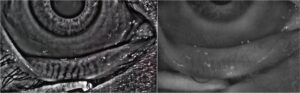

Regelmäßige Anordnung der Meibomdrüsen bei einem gesunden Patienten.

Die Meibographie zeigt den Ausfall des Drüsengewebes an.

Meibographie

Die Infrarotdarstellung der Meibomdrüsen ermöglicht eine Aussage zu diesem für einen funktionellen Tränenfilm äußerst wichtigen Gewebe. Weitere Therapien und die zukünftige Prognose leiten sich aus der Diagnostik ab.